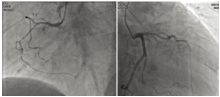

2021-10-09 01∶ 57行心电图示:V1-6导联R波递增不良, V1-5导联ST段弓背抬高, 见图1。2021-10-09 02∶ 33行胸痛指标检测提示:高敏肌钙蛋白T 21.08 pg/mL, B型氨基端尿钠肽原 2 160 pg/mL。遂于2021-10-09 02∶ 50进行冠脉造影, 术中见左主干、右冠未见明显狭窄, 前降支近段狭窄30 %, 钝缘支近段狭窄30%, 见图2。

患者老年男性, 有冠心病高危因素, 急诊入院后结合心电图改变及心肌酶谱表现, 符合急性心肌梗死临床诊断标准, 故第一诊断考虑急性心肌梗死, 行冠脉造影显示前降支和钝缘支轻度狭窄, 左主干、右冠未见明显狭窄, 即排除该诊断。随后经心脏超声发现心尖部异常回声, 考虑心脏肿瘤可能; 完善胸部平扫及增强CT检查, 诊断左下肺肿瘤性病变伴心脏转移可能, 结合肿瘤标志物检查及心包穿刺、纤支镜活检病理明确, 最终诊断为肺癌伴心脏转移。